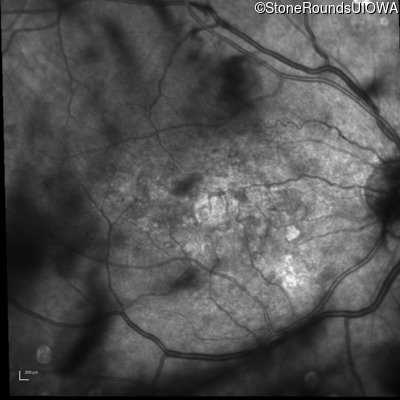

Infrared Fundus Photograph - Right - 20/250

Exemplar